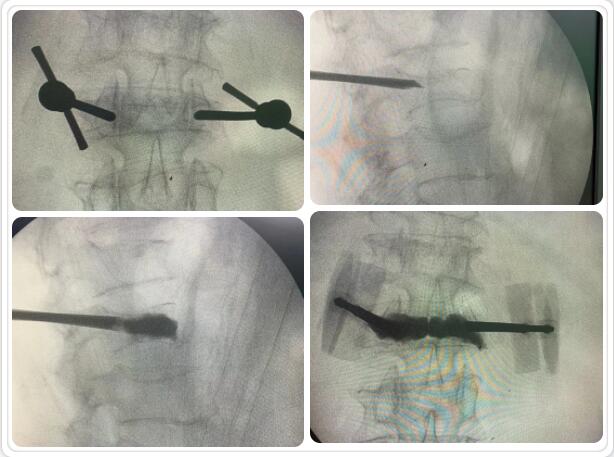

經(jīng)皮椎體球囊擴(kuò)張成形術(shù)是目前臨床治療骨質(zhì)疏松性胸腰椎壓縮骨折的常用方法。椎體成形術(shù)是在局部麻醉和透視下在骨折椎體內(nèi)插入一根或兩根長(zhǎng)針,通過(guò)長(zhǎng)針往椎體內(nèi)注入骨水泥固化骨折部位,維持椎體穩(wěn)定,防止傷椎進(jìn)一步塌陷;同時(shí)骨水泥固化過(guò)程中發(fā)熱導(dǎo)致周?chē)M織壞死、感覺(jué)神經(jīng)末梢毀壞, 產(chǎn)生良好的鎮(zhèn)痛作用。通常術(shù)后第二天即可在支具或腰圍保護(hù)下下床活動(dòng),大大提高了生活質(zhì)量。該微創(chuàng)手術(shù)具有手術(shù)創(chuàng)傷小、起效迅速、安全性高等特點(diǎn),目前已被廣泛應(yīng)用于臨床。

椎體成型(微創(chuàng)手術(shù))過(guò)程